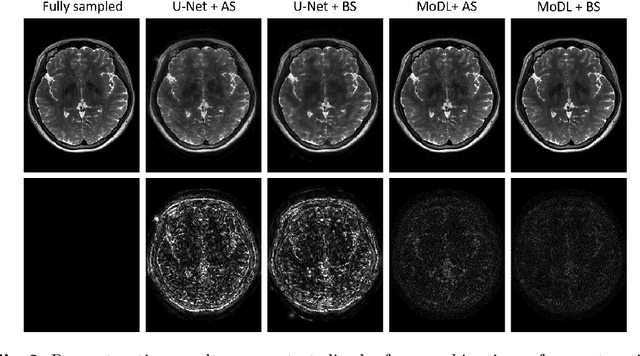

Abstract:The previously established LOUPE (Learning-based Optimization of the Under-sampling Pattern) framework for optimizing the k-space sampling pattern in MRI was extended in three folds: firstly, fully sampled multi-coil k-space data from the scanner, rather than simulated k-space data from magnitude MR images in LOUPE, was retrospectively under-sampled to optimize the under-sampling pattern of in-vivo k-space data; secondly, binary stochastic k-space sampling, rather than approximate stochastic k-space sampling of LOUPE during training, was applied together with a straight-through (ST) estimator to estimate the gradient of the threshold operation in a neural network; thirdly, modified unrolled optimization network, rather than modified U-Net in LOUPE, was used as the reconstruction network in order to reconstruct multi-coil data properly and reduce the dependency on training data. Experimental results show that when dealing with the in-vivo k-space data, unrolled optimization network with binary under-sampling block and ST estimator had better reconstruction performance compared to the ones with either U-Net reconstruction network or approximate sampling pattern optimization network, and once trained, the learned optimal sampling pattern worked better than the hand-crafted variable density sampling pattern when deployed with other conventional reconstruction methods.